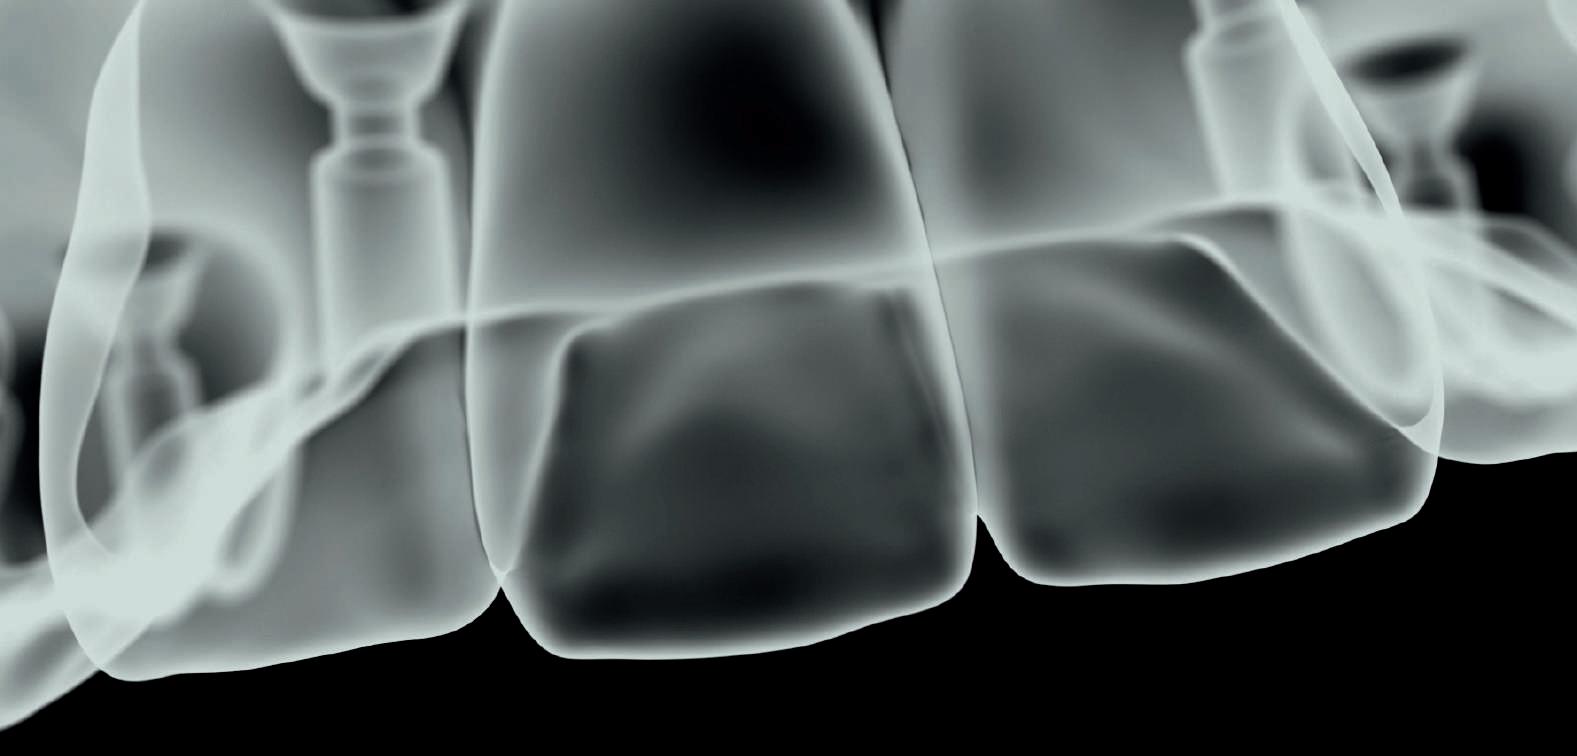

OnX Tough 2 segna una svolta nell'odontoiatria digitale grazie alle sue caratteristiche uniche. È la prima e unica resina certificata per la stampa 3D di protesi ibride fisse, rendendola una scelta senza pari per i professionisti del settore odontoiatrico che cercano soluzioni affidabili e di alta qualità per i loro pazienti. Un aspetto fondamentale di questa resina è la sua radiopacità, essenziale per garantire un monitoraggio accurato delle protesi durante i controlli radiografici, migliorando la sicurezza e l'efficacia dei trattamenti. Inoltre, offre una chiarezza naturale, una traslucenza e una trasmissione della luce superiori, per ottenere risultati estetici di alto livello.

Un'altra caratteristica rivoluzionaria di OnX Tough 2 è la tecnologia NanoFusion, che assicura una distribuzione ottimale delle nanoparticelle ceramiche

all'interno della resina. Questo avanzato processo conferisce alle parti stampate una resistenza e una durezza eccezionali, rendendole ideali per applicazioni esigenti come le protesi ibride fisse.

Oltre a OnX Tough 2, arriva anche Ceramic Crown, una nuova classe di resine da restauro perfetta per piccoli restauri come corone, inlay, onlay e faccette. Composta per oltre il 50% da ceramica e sviluppata per una post-produzione impeccabile, Ceramic Crown non è sem-

plicemente un altro ibrido, ma si tratta di una resina con predominanza di ceramica. Progettato come parte essenziale della soluzione per corone SprintRay, insieme al Crown Kit (che permette di stampare fino a sei corone singole in 15 minuti) e al servizio di Cloud Design AI per corone singole, questo materiale è autorizzato dalla FDA per corone complete, corone parziali e faccette definitive.